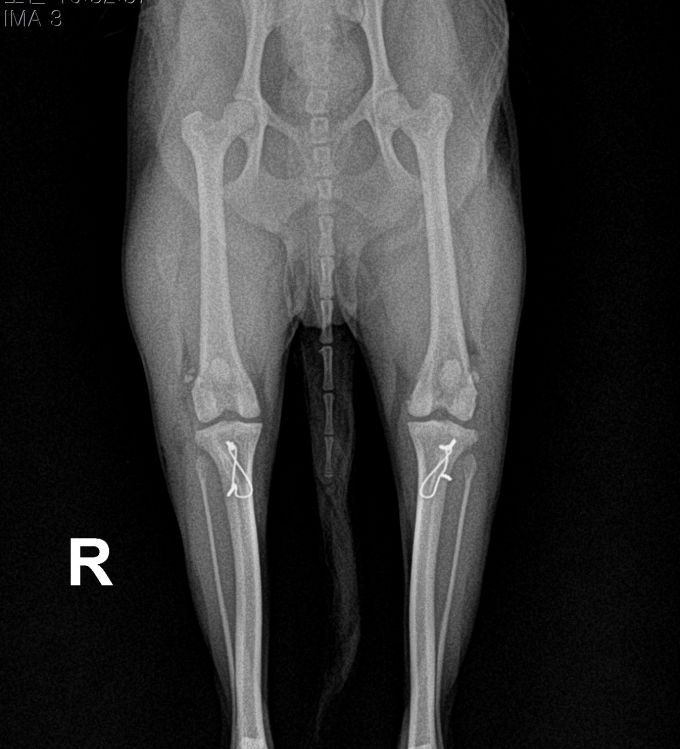

BEFORE

AFTER